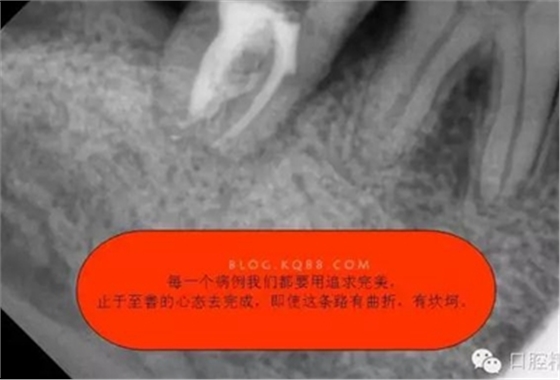

1.拍片基本可以確定遠(yuǎn)中頰側(cè)根管是一個融合根管,也就是常見的C型根管,粗大的根管口是扁形,根管同樣呈扇貝型,根尖孔粗大。而且在根管中上段較粗大,插針拍片后遠(yuǎn)中顯示根管有側(cè)穿的可能,但是通過內(nèi)窺鏡顯示是沒有任何側(cè)穿點(diǎn),也沒有滲血和患者有疼痛現(xiàn)象。這個病例告訴我們,有時候做根管治療,為了把根管做通和預(yù)備到位,必要的牙體組織去除是可以的,后期可以用冠修復(fù)來彌補(bǔ),如果不去除,本病例的根管治療,根充時可能會面臨充填不嚴(yán)密,從而導(dǎo)致根管治療的失敗,這是不可取的。

2.這種C型(2型)根管,在治療的過程中,要注意最重要的兩點(diǎn),一是要在沖洗的過程中用超聲蕩洗,必須用3%次氯酸鈉加雙氧水交替沖洗,因?yàn)镃型根管是不規(guī)則的,要把不規(guī)則的根管沖洗干凈只有超聲蕩洗才能做到。二是充填的時候,要用熱牙膠充填系統(tǒng),只有這樣根管充填才能充填致密,雖然拍X線片會顯示出與常見根管充填不一樣的顯影,但是不規(guī)則的C型根管充填是這種情況,不要被常規(guī)充填結(jié)果所誤導(dǎo)。